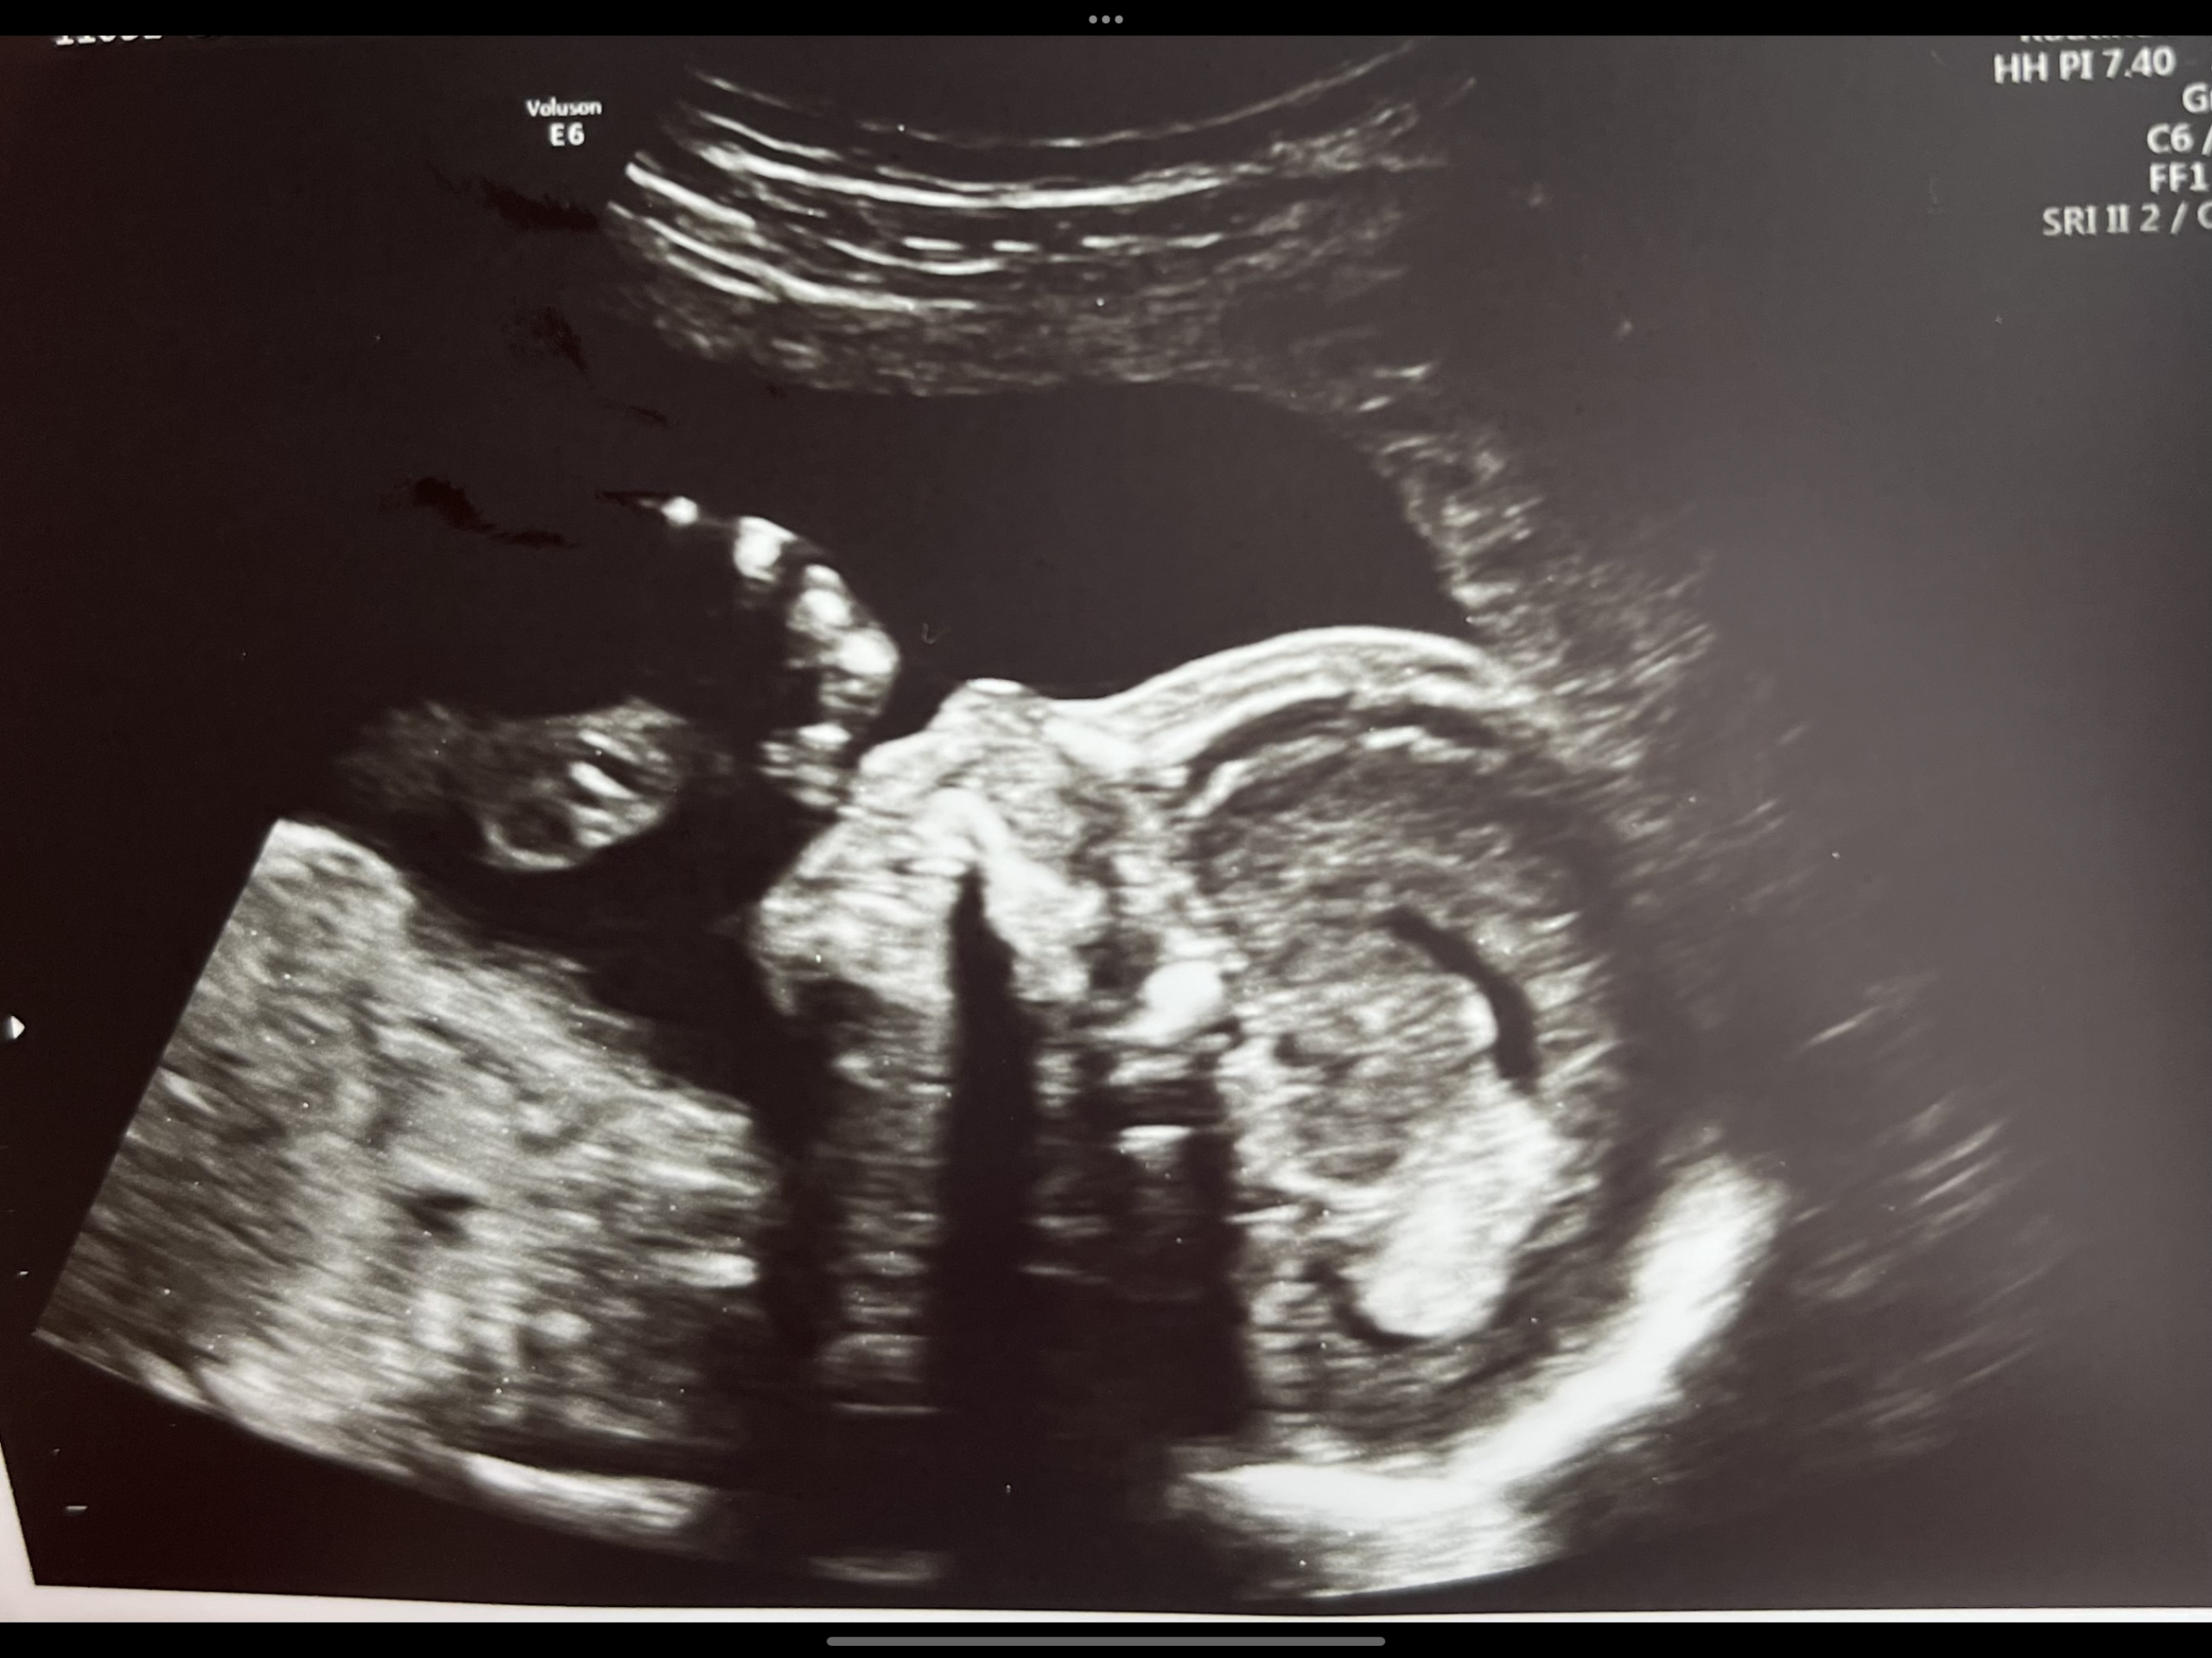

I’m stealing Charlie Kirk’s response from his many debates on abortion. (Here is a great video of him explaining his thoughts). Put 2 ultrasound pictures next to each other, one from a mother who was raped and one from a mother in a loving relationship. There’s no difference, right? So why does one baby deserve to live and the other doesn’t? If the mother does not want the baby or feels she won’t be able to adequately care for the baby, adoption can be an amazing solution! According to American Adoptions, there are approximately 2 million families waiting to adopt. I’m not saying the pregnancy/giving up the baby won’t be hard, I’m sure it will be. But the baby will be given the opportunity for life, and a family will be blessed by them.